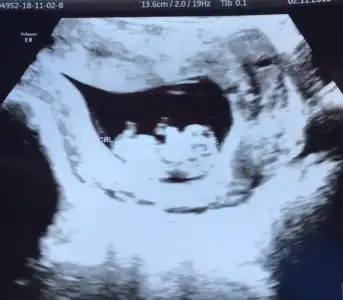

Yaaa cok tatli ama buuuBuraya taşınmışsınız canlarHemen ultrason fotosunu atıyorum size teyzeleri :)

Değil canımm 10 haftalığız daha :) Ne hissettin peki cinsiyet hakkında :)Yaaa cok tatli ama buuutipki anasi

Gecen ne hissetmistim unuttum ama su anda kiz hissediyorum:))Değil canımm 10 haftalığız daha :) Ne hissettin peki cinsiyet hakkında :)

Hadi ya bakalım :) herşeyin hayırlısı ve sağlıklısı tabiki ama kız evlat başka diyorlar sen daha iyi bilirsin tabi :)Gecen ne hissetmistim unuttum ama su anda kiz hissediyorum:))

maşallah Rabbim kucağın almayı nasip etsinBuraya taşınmışsınız canlarHemen ultrason fotosunu atıyorum size teyzeleri :)